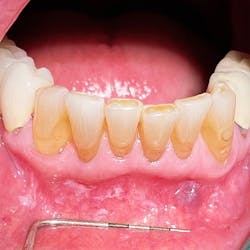

Clinical evaluation revealed scattered, white, creamy patches in the lower anterior vestibule, each measuring approximately 3–6 mm (figure 1). Now, take a look at the second picture after the white patches were easily wiped off with gauze (figure 2). Note the red, thin-membraned tissue? It was very tender to the touch and sensitive even to air.

This diagnosis should be a slam dunk—pseudomembranous candidiasis, aka thrush. Let’s have a refresher.

- Acute pseudomembranous candidiasis consists of creamy, loose patches of desquamative epithelium that are easily removed.1 Red tissue tender to the touch is what is painful to the patient.